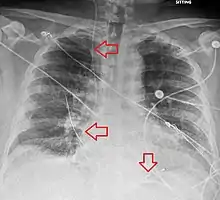

Verify both electrical capture and a pulse of 80 BPM.[4] Usually the device needs to be placed at a depth of 35 to 40 cm.[1] Decrease mA output until capture is lost than double the output to capture again.[1] A chest X-ray is than done to verify placement and rule out some complications.[1] Complications may include heart dysrhythmias and those of placing a central venous catheter, such as pneumothorax.[4]

Post-procedure

An x-ray after the procedure is obtained to confirm placement of the pacing electrode and rule out complications like pneumothorax.[2][4] Defibrillation and cardioversion can still be carried out in someone with a temporary pacemaker.[2]